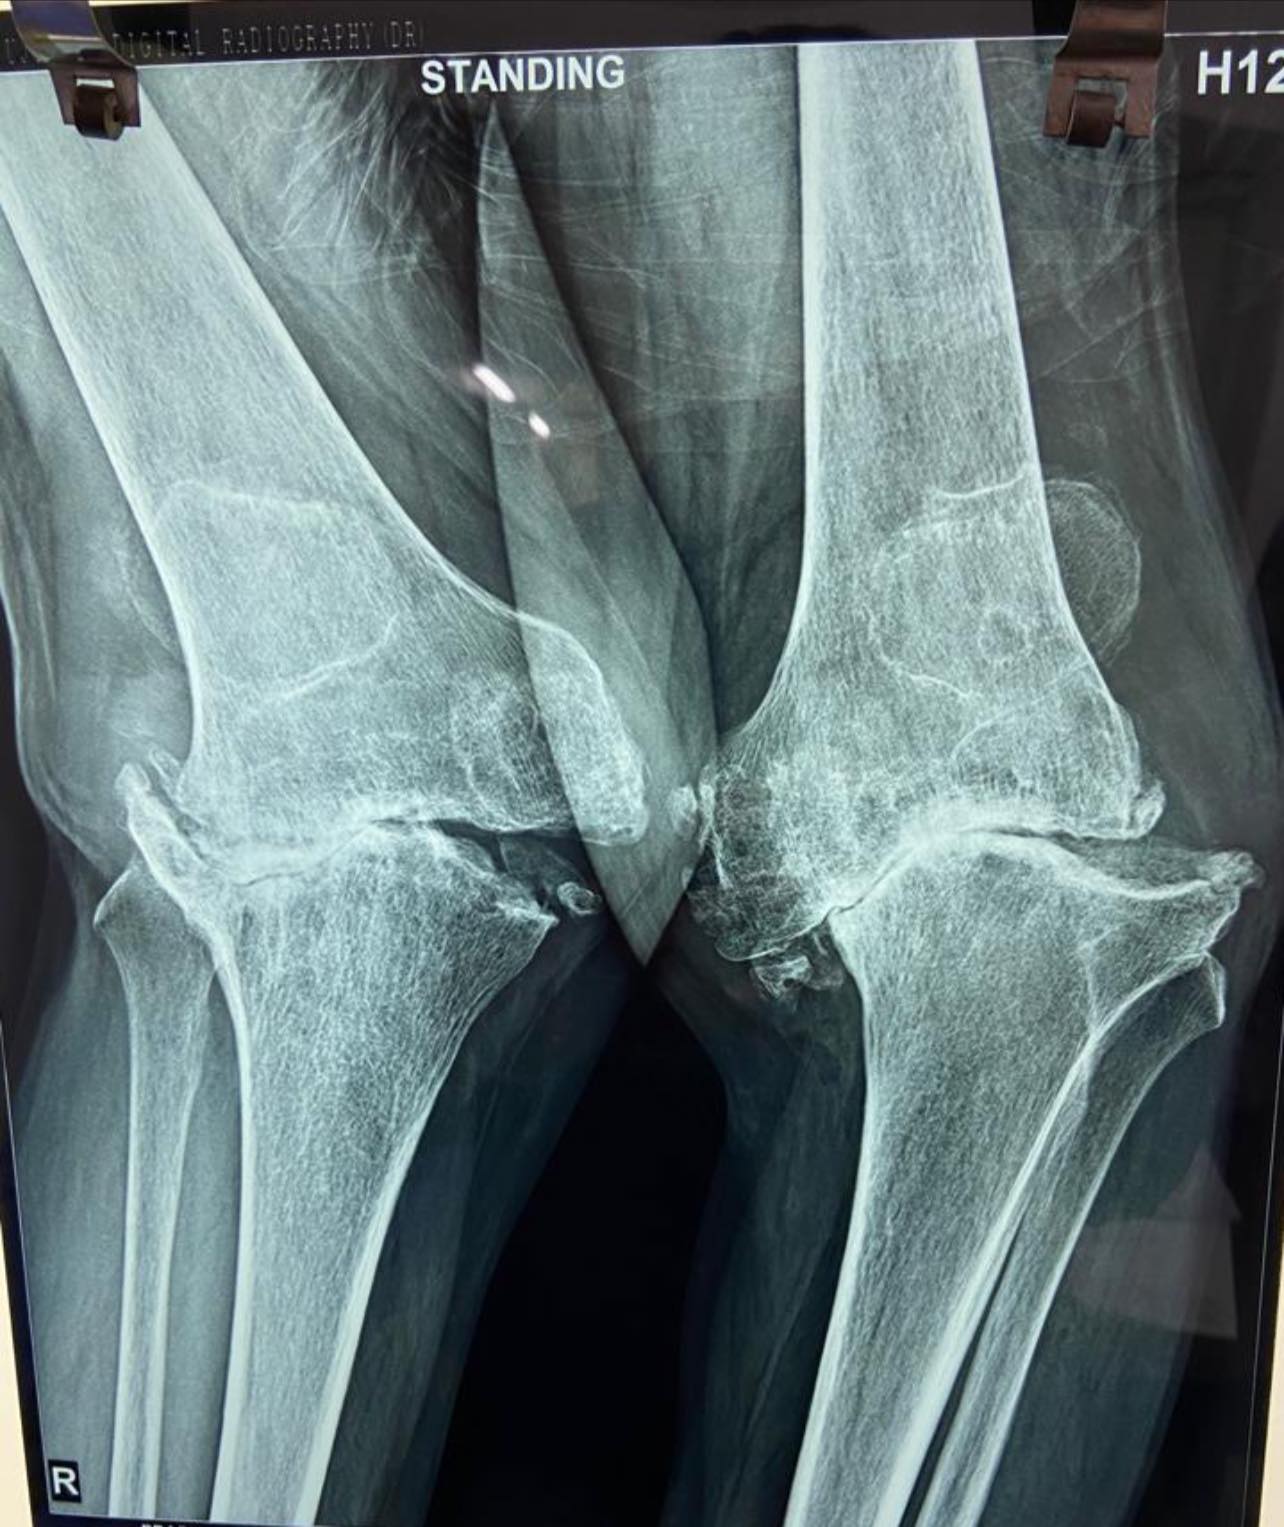

48-year-old male with windswept deformity of knees due to rheumatoid arthritis, both femoral lateral condyles are hypoplastic. Left tibia has a medial bone defect of 20 mm. Treated with long stem prostheses for tkr (total knee replacement) with semi-constrained liners. For the left knee bone defect, bone grafting was done with cc screw fixation.